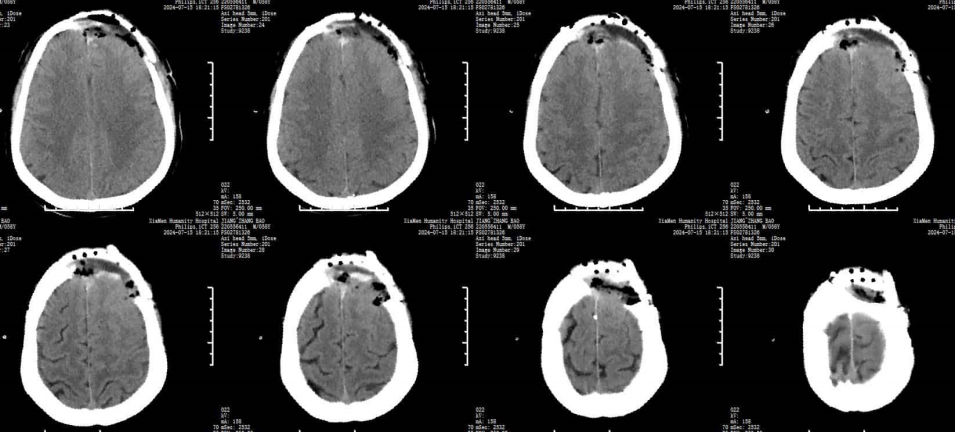

CT

術后頭顱CT:腫瘤全切